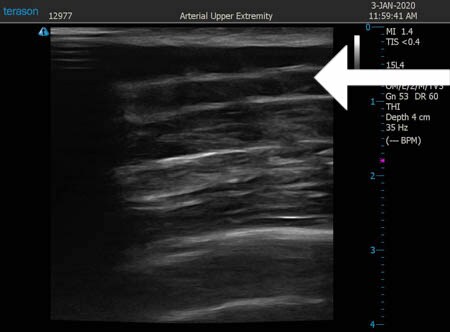

いつものように3Dタッチビュー(超音波)で

皮下脂肪層を評価してみましょう。

左肩甲骨横

↓ ↓ ↓